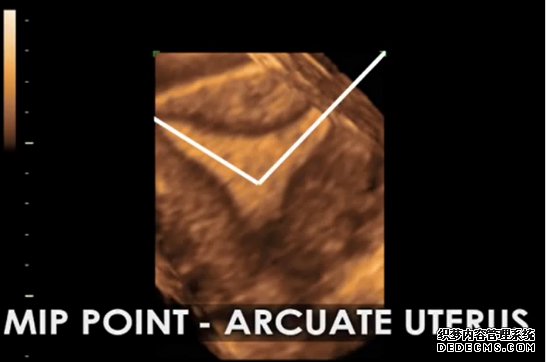

完美的最佳植入点定位技术。利用最新型的3D-4D辅助彩超技术,笙笙试管中心可以完美捕捉正常子宫、畸形子宫的最佳植入位点,为完美着床和完美受孕做好技术保障。